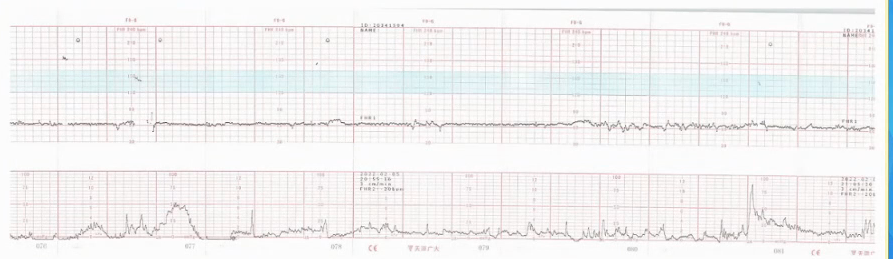

3)可疑OCT阳性:下面图纸显示不协调的宫缩、散在的VD波、超过30min的变异减速。如果病人没有真正临产、OCT阳性和可疑阳性,需要宫内复苏同时选择剖宫产。

胎监cst是什么【温故知新】熟悉电子胎心监护判读要点,正确掌握胎监图纸解读六步法_https://www.jmylbn.com_新闻资讯_第3张

胎监cst是什么【温故知新】熟悉电子胎心监护判读要点,正确掌握胎监图纸解读六步法_https://www.jmylbn.com_新闻资讯_第41张